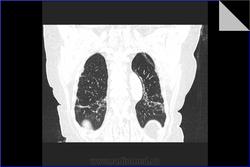

Идиопатический фиброзирующий альвеолит. Пациентке 79 лет. Диагноз поставлен 3 года назад. Лечится гормонами. Клинически за 3 года наросла одышка. Данные прошлых исследований не предоставлены. Заинтересовали размеры легочной артерии. Основной ствол - 37 мм (N=29 мм), правая ветвь 33 мм (N=24 мм), левая ветвь 28 мм (N=28 мм). Интересно, почему степень расширения левой легочной артерии отстает от правой и основного ствола. Обусловлено ли это разными углами отхождения ветвей или может косвенно характеризовать степень вовлеченности легочной ткани каждого легкого в фиброзирующий процесс?

Идиопатический фиброзирующий альвеолит. Пациентке 79 лет. Диагноз поставлен 3 года назад. Лечится гормонами. Клинически за 3 года наросла одышка. Данные прошлых исследований не предоставлены. Заинтересовали размеры легочной артерии. Основной ствол - 37 мм (N=29 мм), правая ветвь 33 мм (N=24 мм), левая ветвь 28 мм (N=28 мм). Интересно, почему степень расширения левой легочной артерии отстает от правой и основного ствола. Обусловлено ли это разными углами отхождения ветвей или может косвенно характеризовать степень вовлеченности легочной ткани каждого легкого в фиброзирующий процесс?

Для легочного идиопатического фиброза = криптогенного фиброзирующего альвеолита изменения не выражены - может, адекватная терапия. Либо одышка и ДН по другой причине. Если брали биопсию - вопросов нет, а если нет, то есть)))